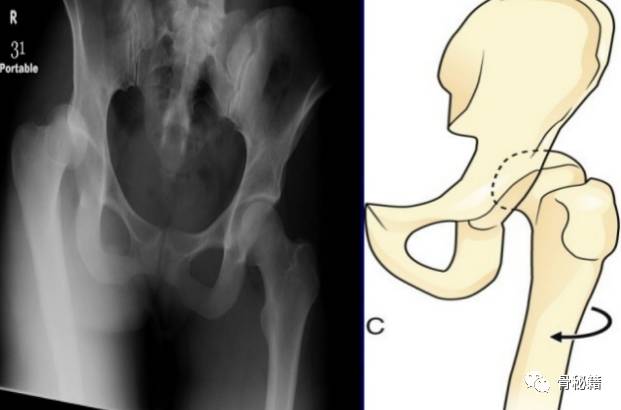

髋关节脱位主要分为后脱位和前脱位,80%都为后脱位

最常见的仪表盘类损伤常伴随后脱位,需要行X线进行脱位的确诊

后脱位有的是由旋转暴力,有的是由垂直暴力所引起

2、具体的临床表现内收、屈曲、内旋